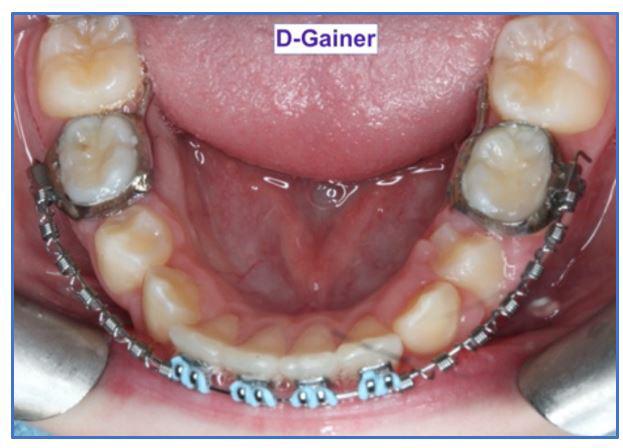

Tips from the Experienced: The D-Gainer Appliance, Pt. 1, By Dr. Adrian J. Palencar, MUDr, MAGD, IBO, FADI, FPFA, FICD

The maxillary cuspids were erupting mesially to the lateral incisors, with very little space to accommodate both teeth without an odontectomy. The expansion was continued (1/4 turn 2x per week), and an attempt was made to create more space for erupting cuspids with an open coil spring (OCS) – between the central incisors and the cuspids (Molar distalization spring, a .010 x .045 - Ortho Organizers). The OCS was measured and cut 4.0 mm longer than the available space. The maxillary arch wire was a .018 SS. An elastomeric chain (EC) was attached from the Hyrax to the lingual button on the lateral incisors. It was necessary to first pull the lateral incisors away from the alveolar process to prevent the break down of the buccal cortical bone around the cuspids (Figure

B, C).